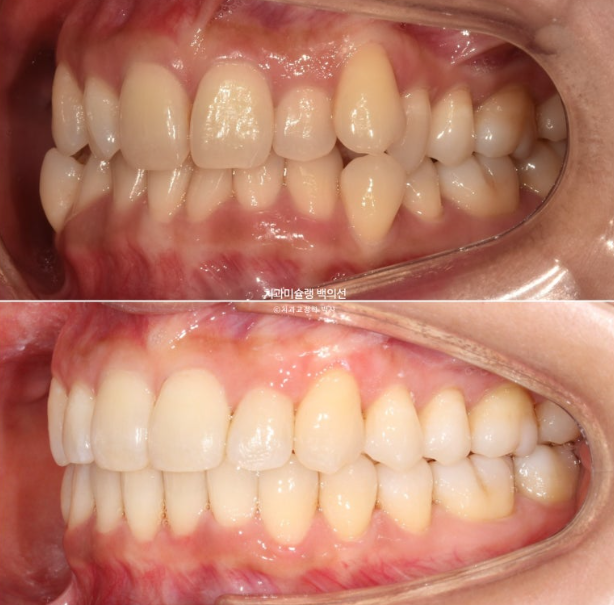

24.08~25.08

옥니였던 앞니 각도가 정상각도를 찾았습니다.